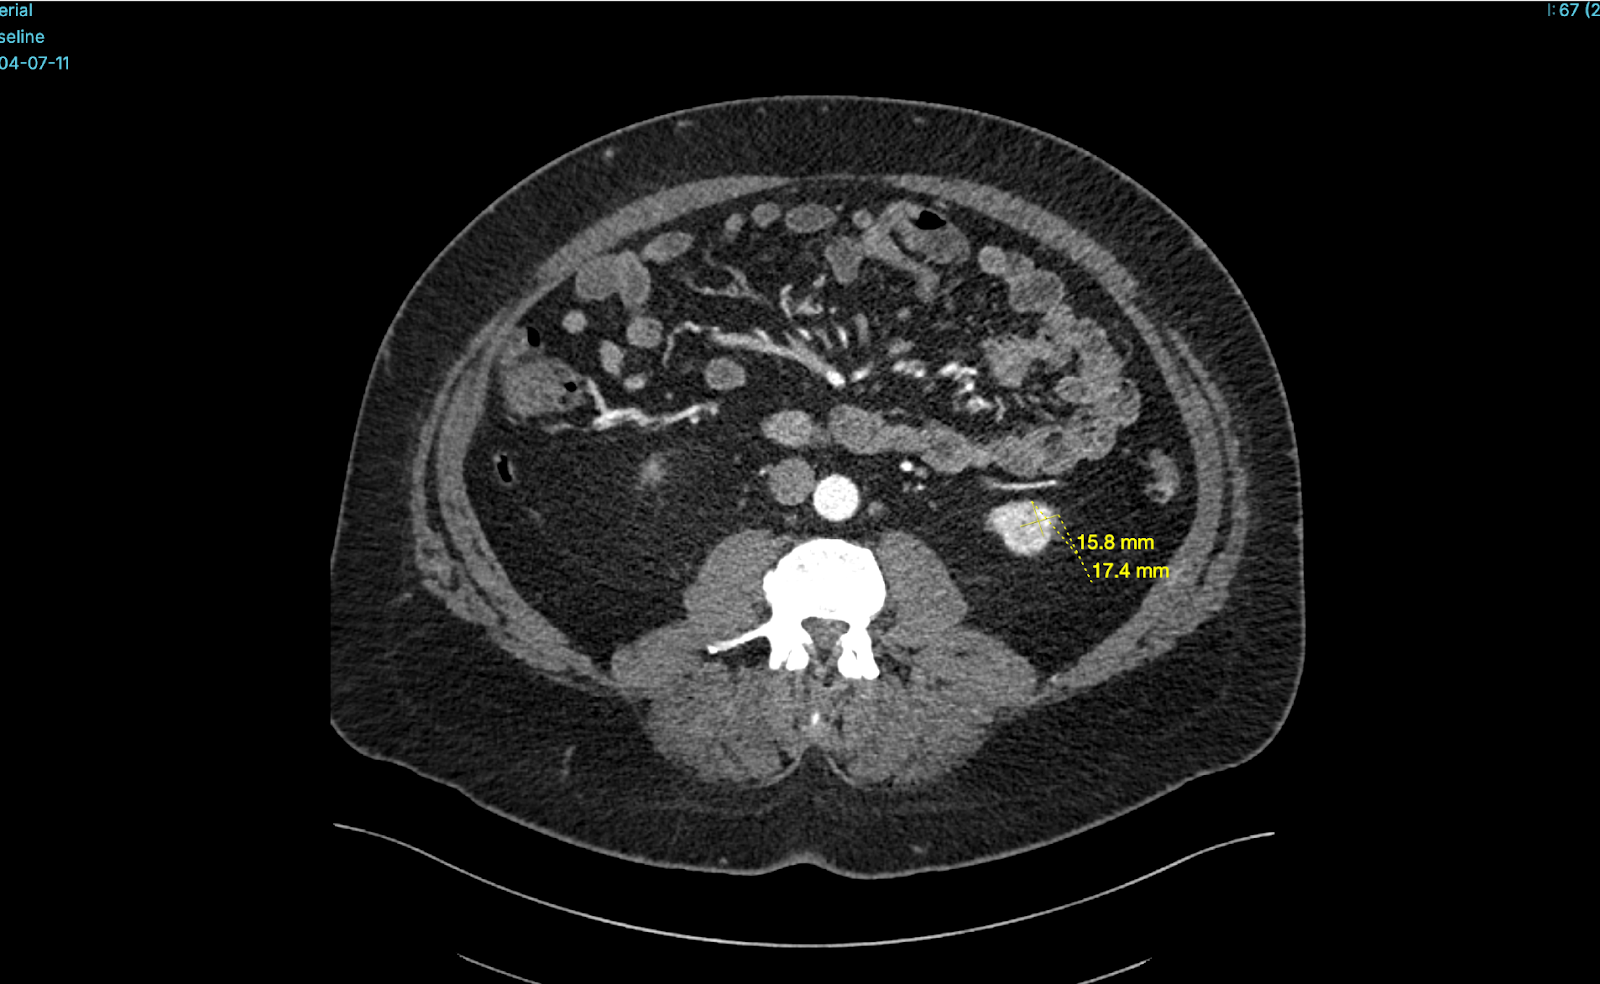

Better Medicine provides an AI-powered radiology solution, BMVision Kidney, designed to enhance diagnostic consistency and speed in kidney cancer detection. It is the first and only CE-certified AI model specifically trained to identify renal tumours from CT scans.

The software runs fully on-premise within UMC’s infrastructure, integrates with existing PACS and viewer systems, and processes CT data in standard formats to deliver interpretable results. Using advanced deep learning, BMVision Kidney automatically detects, segments, and characterises kidney lesions—including incidental findings—with accuracy comparable to radiologists. The solution strengthens diagnostic reliability, reduces variability, and supports faster, more consistent clinical decision-making within UMC’s radiology workflow.